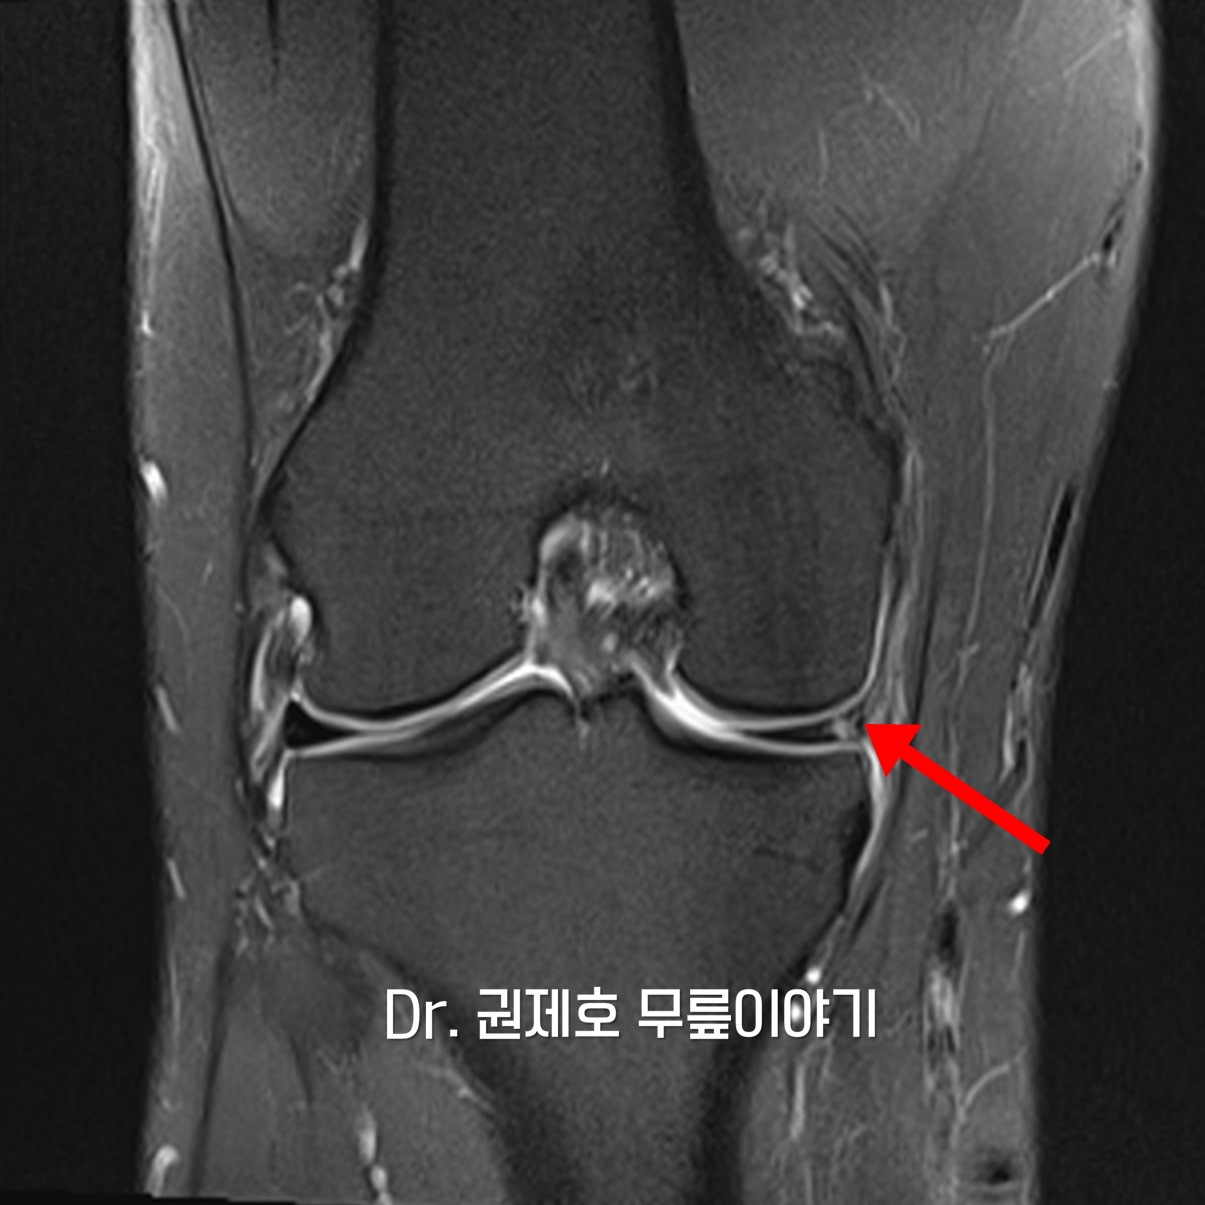

무릎 MRI 검사를 통해 무릎 속에 구조물들 중에서 어떤 것에 문제가 있는지 확인하게 되는데, 검사 결과 무릎연골판이 방사형파열이 있음을 확인하였다.